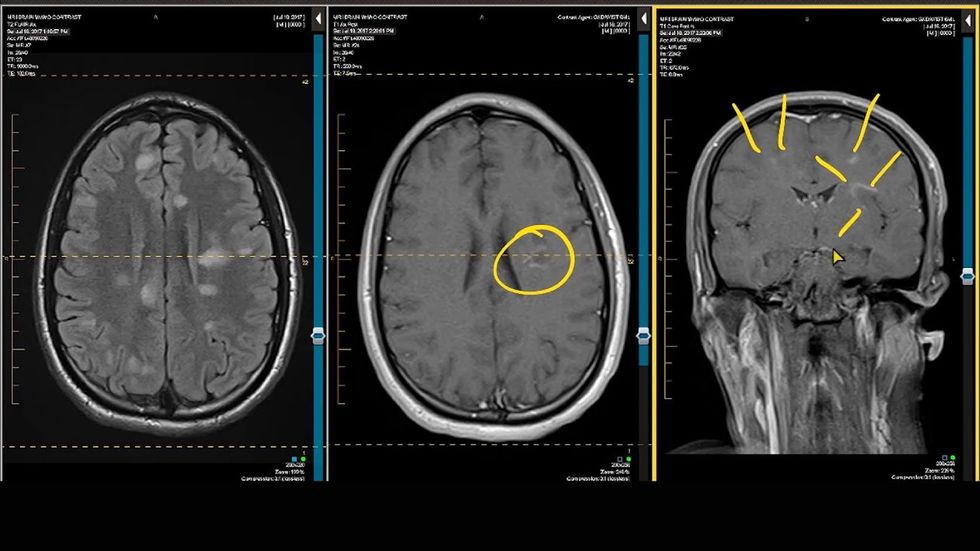

Shtatë shenjat e hershme të sklerozës - njihini ato në kohë

Simptomat e sklerozës së shumëfishtë mund të shfaqen që në të njëzetat, duke u shfaqur dhe zhdukur në intervale të parregullta. Sipas Shoqatës së Sklerozës Multiple të Amerikës, më shumë se dy milionë njerëz në mbarë botën vuajnë nga kjo sëmundje